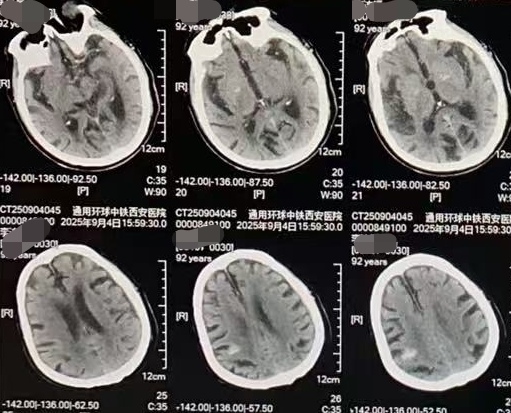

头颅CT提示少量出血

脑科病院院长王建强团队凭借丰富的临床经验,初步考虑为急性脑卒中,定位高度怀疑基底动脉栓塞。时间就是大脑!脑卒中绿色通道立即开启,快速完善头颅CT检查,提示右侧额顶叶脑出血、少量蛛网膜下腔出血,出血量约5ml,出血病灶与初步定位诊断存在差异。但团队综合评估后,仍坚持脑栓塞的核心诊断方向,为明确病变关键信息,拟进一步行脑血管造影检查。